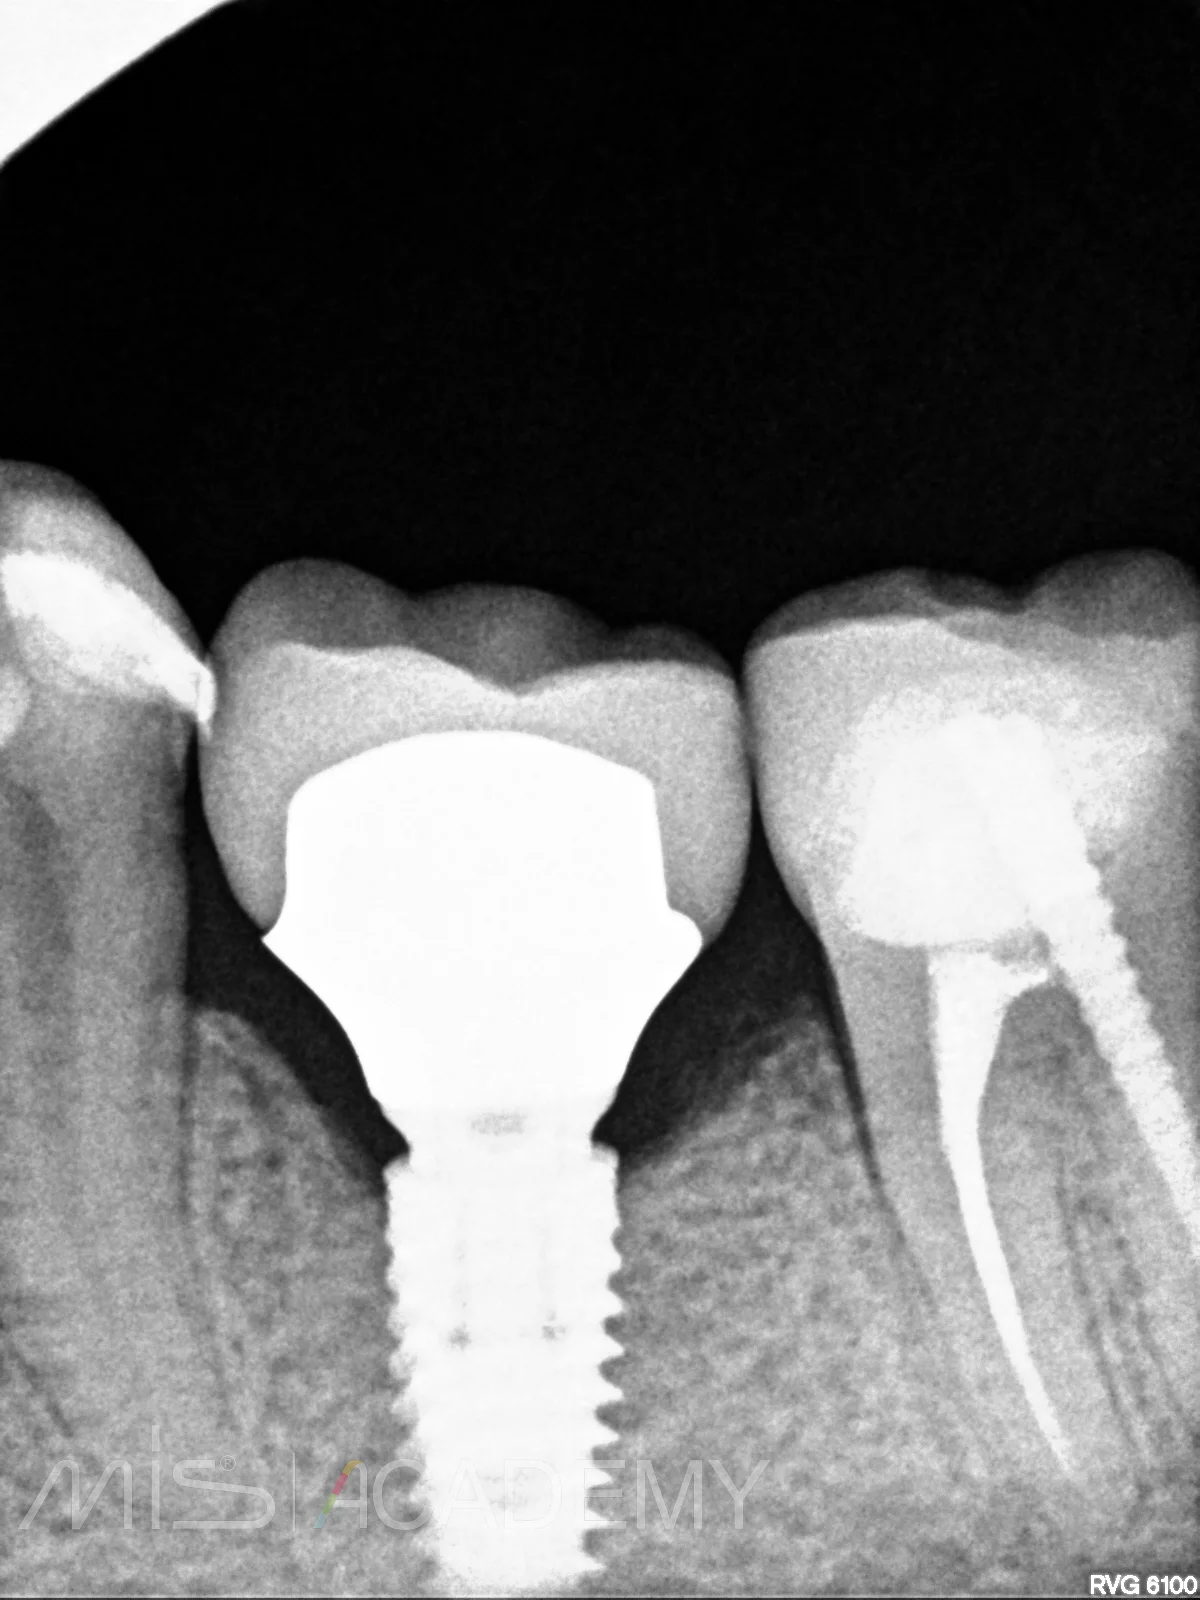

— Далее провизорное протезирование и постоянная конструкция на цементной фиксации коронки из дисиликата лития на гибридном абатменте.

— Дистальный моляр тоже покрыли коронкой из дисиликата лития, а вот премоляр пациентка отказалась (На рг снимках ситуация после фиксации и через 2 года. Вроде как даже кортикализация произошла.